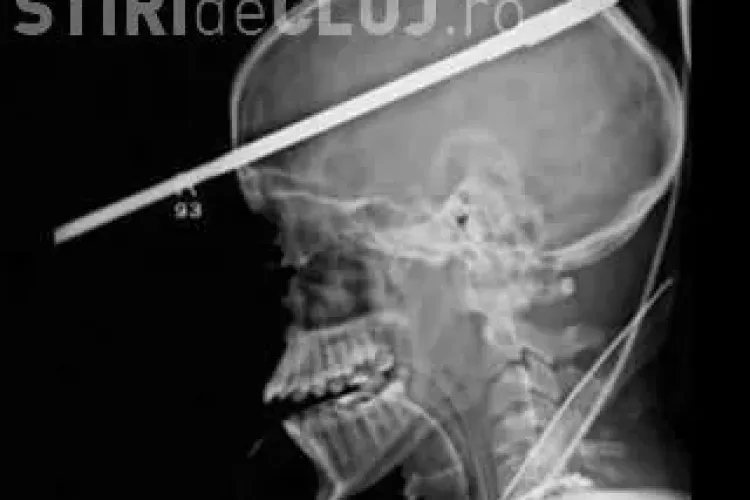

Angajaţii unui aeroport din Roma au înlemnit când au privit imaginea de pe monitor

Angajaţii de la securitatea aeroportului Fiumicino din Roma au fost şocaţi când au pe monitor un corp uman.